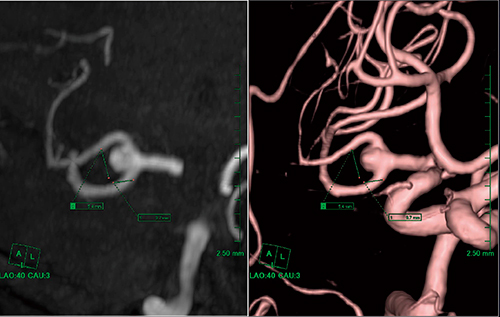

(4)VRまたはMIPを右ドラッグしながら測定点(動脈瘤)を赤い点に合わせる(図5)。

図5 測定点の設定

(5)VRまたはMIPで動脈瘤の長短軸が見やすいアングルに合わせ,長軸および短軸径を計測する(図6)。

図6 長短軸径の計測